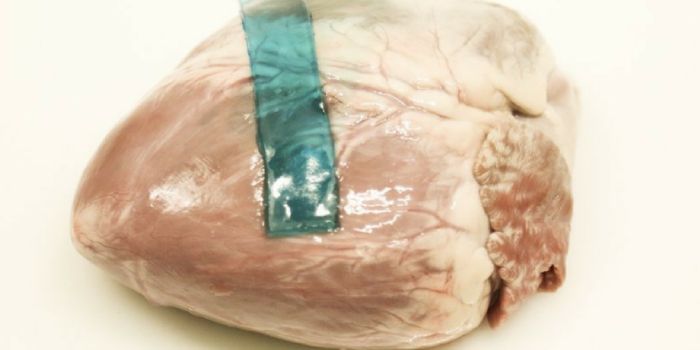

APR 16, 2016Clinical & Molecular DXMIT researchers recently engineered a flexible polymer implant that can directly release chemotherapy drugs to pancreati ...

OCT 10, 2017Clinical & Molecular DXWe’ve all experienced the annoying Band-Aid that won’t stay on when wet. And when it comes to bigger cuts an ...

JUL 31, 2017Clinical & Molecular DXWe’ve all experienced the annoying Band-Aid that won’t stay on when wet. And when it comes to bigger cuts an ...